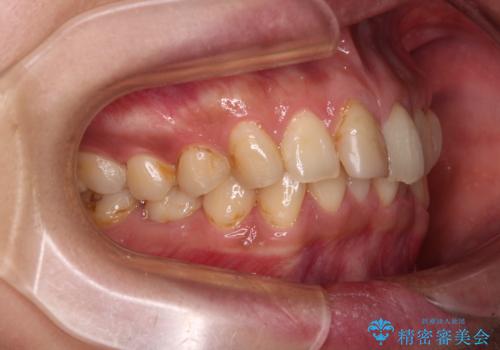

- 全体的なデコボコと左下乳歯部の欠損を気にして来院された患者様です。

乳歯が抜け落ちた後の後続永久歯が欠損しているため、スペースが残っておりました。

口元の突出感を気にしているのであれば欠損スペースを利用して抜歯矯正を行うことも可能ですが、横顔の印象はスッキリとしている状態であったため、矯正治療でスペースを閉じきることは不可能と判断し、インプラントによる補綴治療を行うこととしました。

第二小臼歯の欠損によるが乳歯残存や欠損が多く、この乳歯は後続永久歯に比べて幅が非常に大きいため、教聖地料によるスペースクローズが難しいことが一般的です。